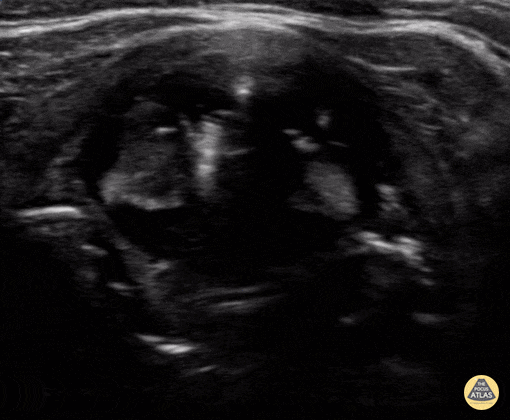

Intubation attempt into the esophagus of an 8 year old male with respiratory distress. Notice the soft tissue posterior to the trachea moving with the provider attempting the pass the tube. Zach Boivin, MD, @ZachBoivinMD